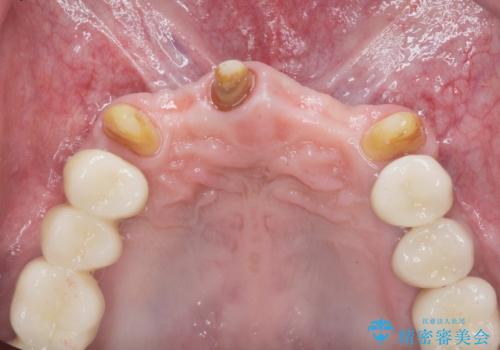

インプラント・ブリッジ補綴を含む、歯周病全顎治療

- 歯が全体的に揺れ始め、恐怖を感じ他院に相談に行ったところ、全体的な歯周病の問題・抜歯の必要性・入れ歯の提案を受け、入れ歯以外の選択肢を希望され来院されました。

全体的な歯周病検査を行い、多数の残すことのできない抜歯の必要な歯を認めたため、残せる歯に対しての徹底的な歯周病治療、失った歯に対しブリッジ・インプラント治療を全顎的に行っていくこととしました。